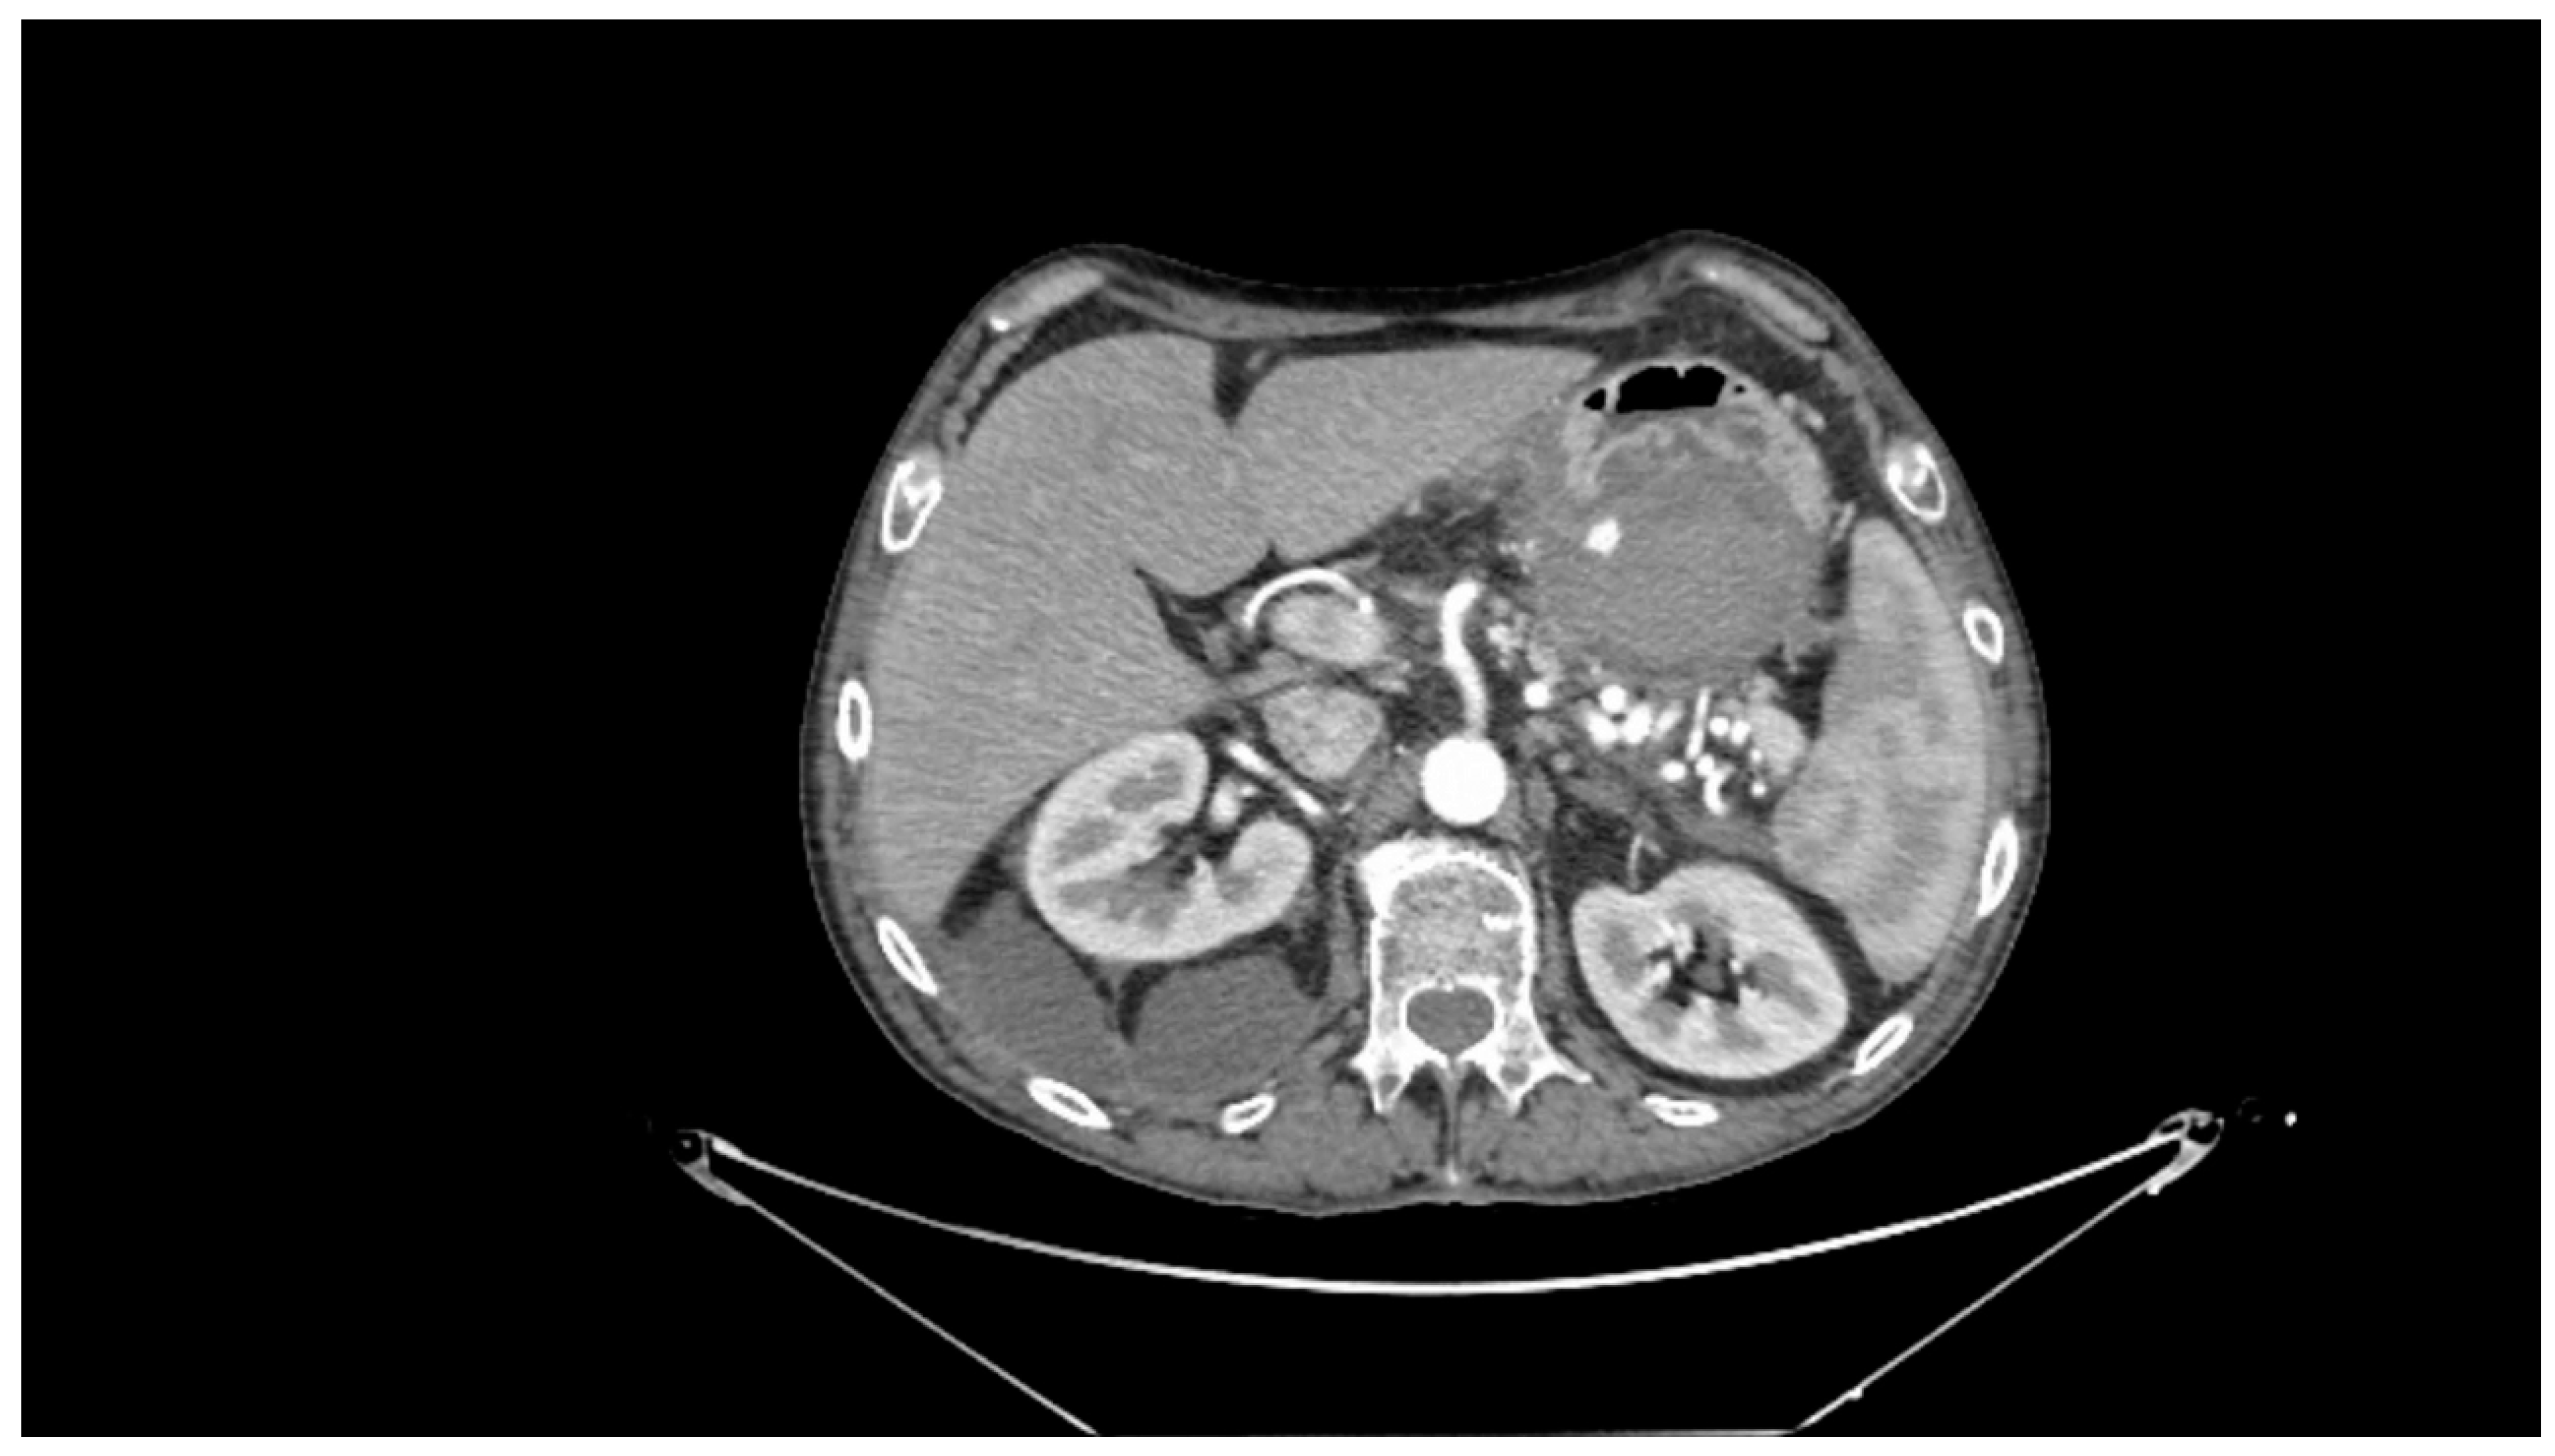

Contrast-enhanced CT scan remains a fundamental study for diagnosing complications of pancreatitis, including bleeding [31]. In cases of acute hemorrhagic pancreatitis, unenhanced CT typically shows significant enlargement of the pancreas with areas of low attenuation. After intravenous contrast administration, the pancreas displays irregular contrast enhancement, indicating areas of normal perfusion (i.e., viable parenchyma) and regions of reduced or abnormal perfusion (i.e., suggesting edema or necrosis) [21,31,39]. In cases of direct vascular damage or intraluminal bleeding, extravasation of contrast material can be seen, a highly specific finding for active bleeding (Figure 2) [31,40].

Figure 2. Contrast-enhanced abdominal computed tomography showing active bleeding inside a peripancreatic collection. Reproduced with permission from Bellio, G., et al. [29].